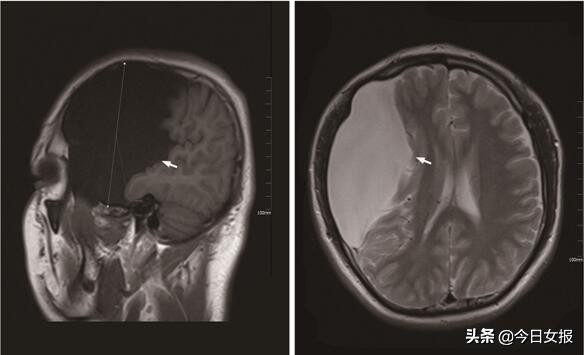

为进一步明确手术方案,确保患者安全,手术组决定为小彭进行头颅磁共振检查,果然发现小彭颅内巨大蛛网膜囊肿,内为水样液体,最大直径达到12厘米,几乎占据了一侧大脑半球的一半,并明显的压迫脑组织。

医院神经内科黄远桃副主任医师在会诊中介绍,患者颅内达到12厘米大的蛛网膜囊肿非常罕见,因压迫脑组织的过程非常缓慢,所以头痛、视力和记忆力下降、抽搐等头部症状才不明显。